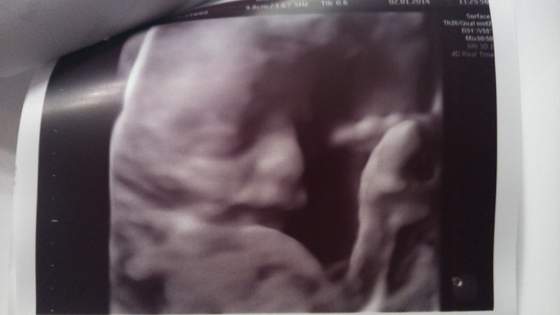

super że wszystko okZ USG jestem bardzo zadowolona pani ktora wykonywala badanie byla bardzo bardzo dokladna co sobie chwale obejrzala naszego synka wzdluz i wszerz zrobila piekne wszystkie pomiary

Potwierdzila Nam Chłopczyka takze juz dwoch lekarzy powiedzialo to samo i wdzialam to samo

Maly wydawal sie spokojny i zrelaksowany tylko buski nie dal sobie zrobic na zdjeciu co pani chciala mu zrobic zdjecie to sie wysunol z klatki i nie widac go zbyt wyraznie na zdjeciach. szkoda niespodzianka z buska do porodu bedzie

a to nasze wymiary ;

20+6 tygodnia

HC= 177mm

TCD= 160mm

PV= 20,3mm

AC=160mm

FL= 32,7mm

Rozwija sie prawidlowo dla danego wieku ciazy.

Widoczne narzady

-Głowa

-Twarz

-Serce bije prawidlowo 4 komory serca widoczne i przeplyw krwi jest prawidowy

-Klatka piersiowa

-Nerki

-Pęcherz

-Kregosłup itp wszystko na swoim miejscu pracuje i rozwija sie jestem mega szczesliwa i zadowolona i spokojna aby do porodu i ujrzec swego upragnionego Syna